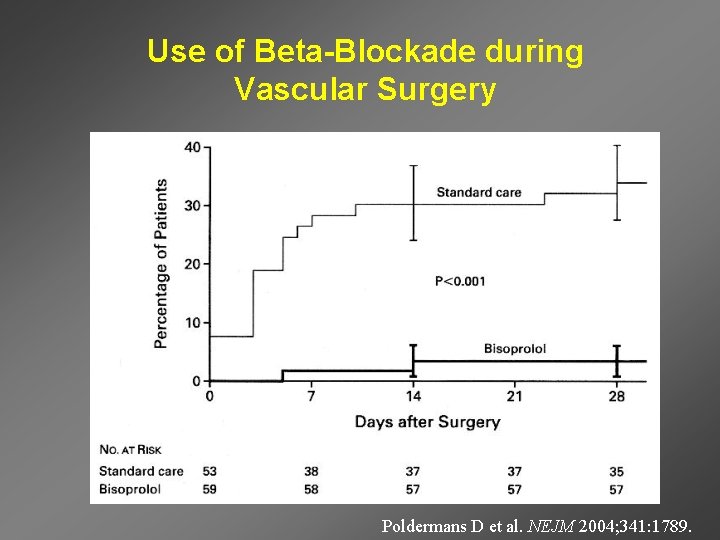

Use of Beta-Blockade during Vascular Surgery Poldermans D et al. NEJM 2004; 341: 1789.